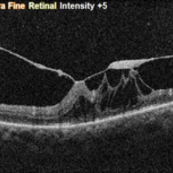

RPE rip in a case of Idiopathic polypoidal choroidopathy RPE rip in a case of Idiopathic polypoidal choroidopathyOct 23 2022 by Anjana Mirajkar, MS Ophthalmology OCT image in a of 61 year old male with RPE rip in a case of Idiopathic Polypoidal Choroidopathy. Photographer: Dr. Anjana Mirajkar -Retina Foundation, Ahmedabad Condition/keywords: Idiopathic polypoidal choroidopathy, RPE rip